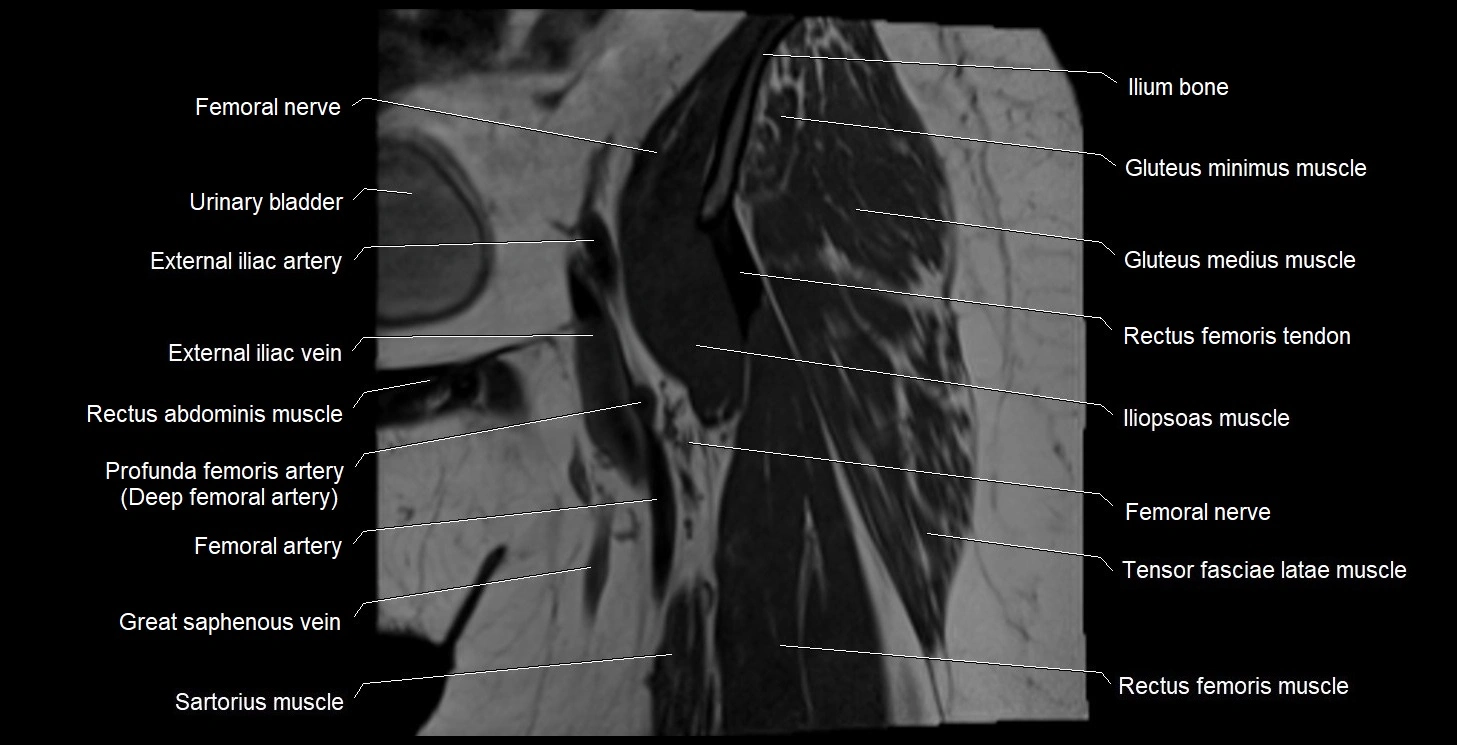

- Deep femoral artery (profunda femoris)

- External iliac artery

- External iliac vein

- Femoral artery

- Femoral nerve

- Femoral vein

- Gluteus medius muscle

- Gluteus minimus muscle

- Iliopsoas muscle

- Ilium bone

- Pectineus muscle

- Pubic bone

- Rectus femoris muscle

- Rectus femoris tendon (Proximal tendon of rectus femoris)

- Sartorius muscle

- Tensor fasciae latae muscle

- Urinary bladder

- Vastus intermedius muscle

- Vastus lateralis muscle

- great saphenous vein